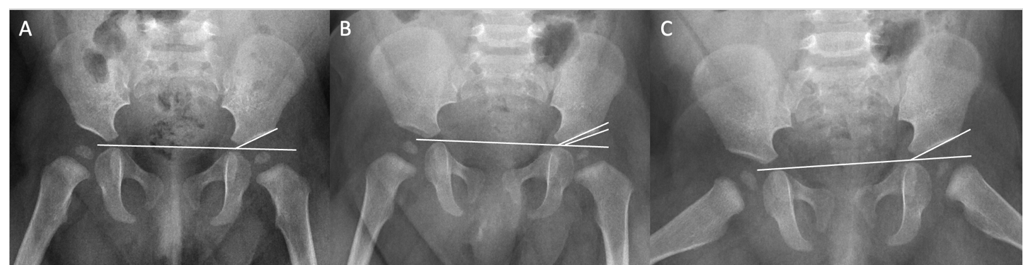

Frog-Leg Lateral Pelvic Radiographs are Reliable for the Measurement of Acetabular Index in Developmental Dysplasia of the Hip